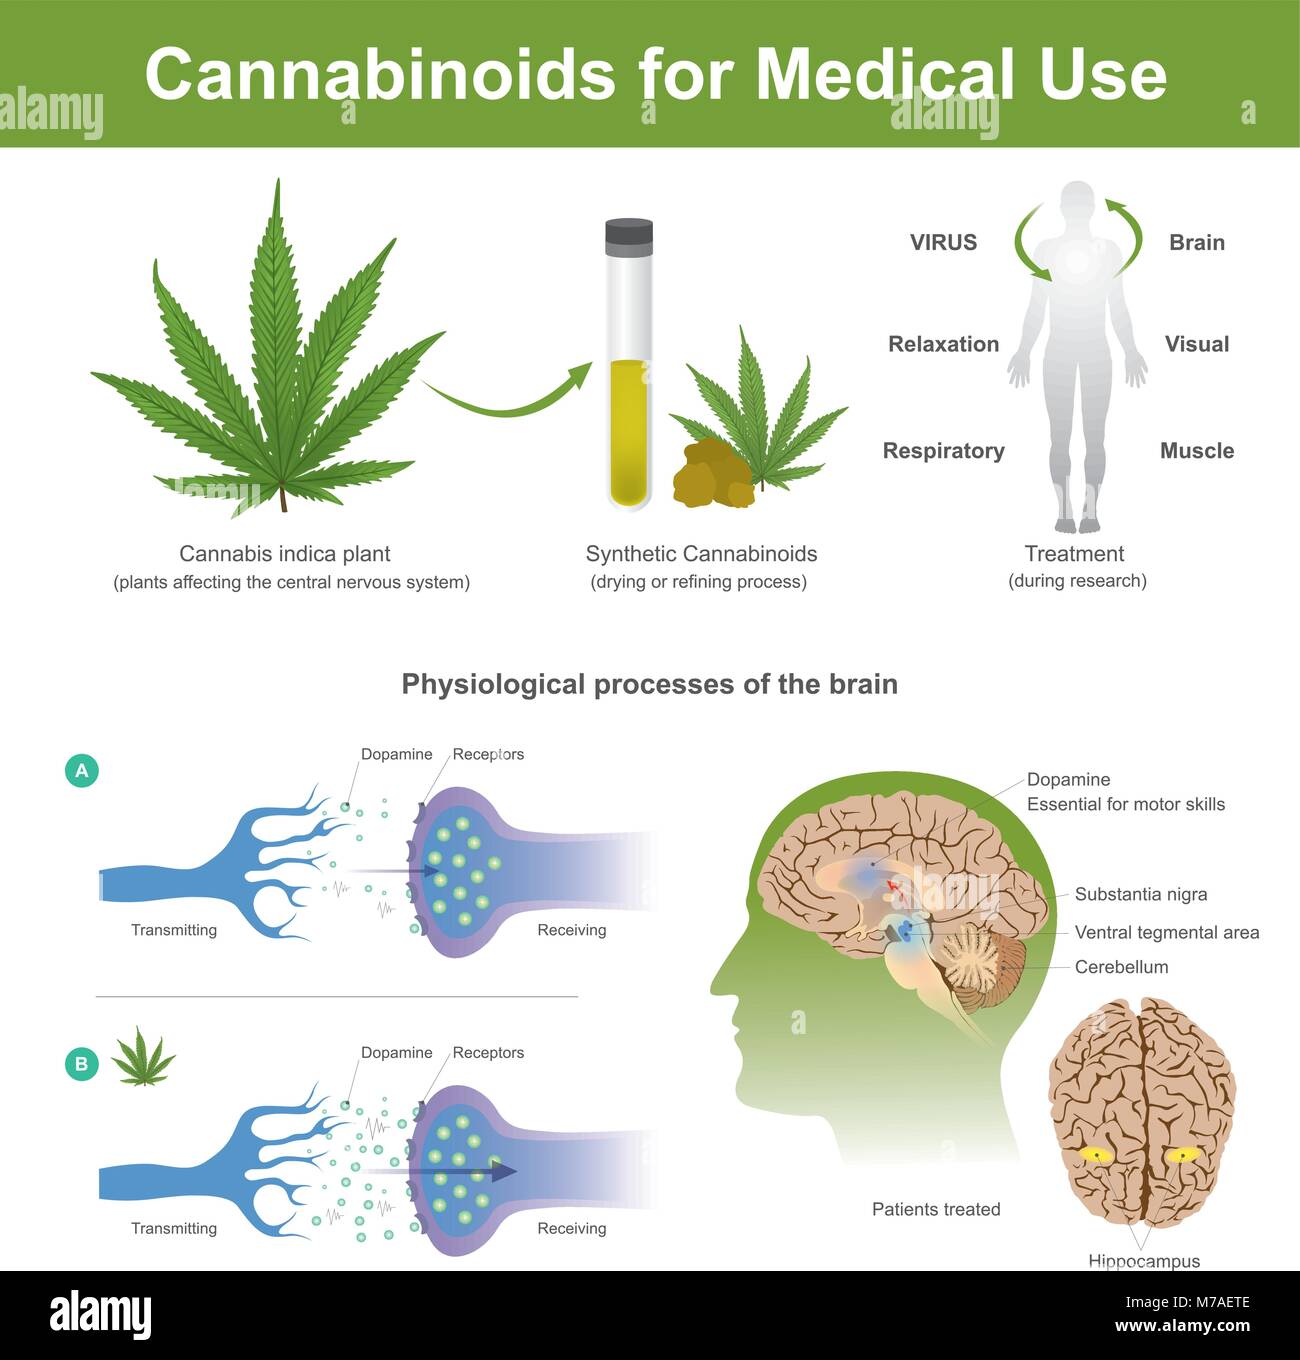

La ricerca ha trovato che la cannabis indica pianta può avere i seguenti effetti Cannabis è pianta che colpisce il sistema nervoso centrale nell'uomo. Illustrazione Vettorialehttps://www.alamy.it/image-license-details/?v=1https://www.alamy.it/foto-immagine-la-ricerca-ha-trovato-che-la-cannabis-indica-pianta-puo-avere-i-seguenti-effetti-cannabis-e-pianta-che-colpisce-il-sistema-nervoso-centrale-nell-uomo-176637454.html

La ricerca ha trovato che la cannabis indica pianta può avere i seguenti effetti Cannabis è pianta che colpisce il sistema nervoso centrale nell'uomo. Illustrazione Vettorialehttps://www.alamy.it/image-license-details/?v=1https://www.alamy.it/foto-immagine-la-ricerca-ha-trovato-che-la-cannabis-indica-pianta-puo-avere-i-seguenti-effetti-cannabis-e-pianta-che-colpisce-il-sistema-nervoso-centrale-nell-uomo-176637454.htmlRFM7AETE–La ricerca ha trovato che la cannabis indica pianta può avere i seguenti effetti Cannabis è pianta che colpisce il sistema nervoso centrale nell'uomo.